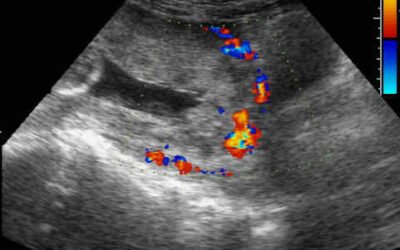

A multidisciplinary team as an intervention to improve maternal and perinatal outcomes in placenta accreta spectrum (PAS)

Placenta accreta spectrum (PAS) is associated with maternal morbidity & mortality and with Cesarean Section as a risk factor which continues to increase globally